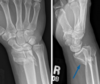

**Colles - ‘dinner fork type deformity’** Features of the injury 1. Transverse fracture of the radius 2. 1 inch proximal to the radio-carpal joint 3. Dorsal displacement and angulation of the distal radius

34

Colles fracture ## Footnote Typically FOOSH forwards Extra-articular radial # with dorsal (posterior / back of hand) angulation and displacement

Smith Fracture ## Footnote Typically FOOSH back of hand Extra-articular radial # with volar (anterior / palmar) angulation and displacement